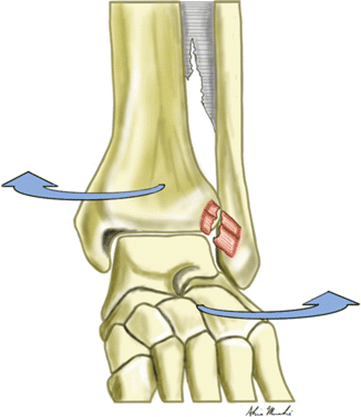

When you twist your ankle you can sustain a number of injuries and unfortunately only broken bones can be seen on an x-ray which is the most common first-line investigation. Sometimes a small “flake” or “chip” of bone can be seen on the outside of the ankle which does not look too concerning. This can however be the attachment site of an important ligament and not having any treatment can lead to an unstable ankle that gives way in the long term.

Even if there is not a chip of bone the ligaments on the outside of the ankle can be stretched or torn and although surgery can usually be avoided it is really important to understand the injury and put into place a good rehabilitation plan.

Sometimes the ligaments on the inside of the ankle are also injured. Again, surgery can usually be avoided but understanding the diagnosis is the key to effective and successful rehabilitation. Another common cause of ongoing pain after an ankle sprain is an injury to the joint between the two leg bones known as the syndesmosis. If the injury is acute this can be picked up on MRI, however, if it has been going on for more than a few months a diagnostic arthroscopy is the best way to assess this area.